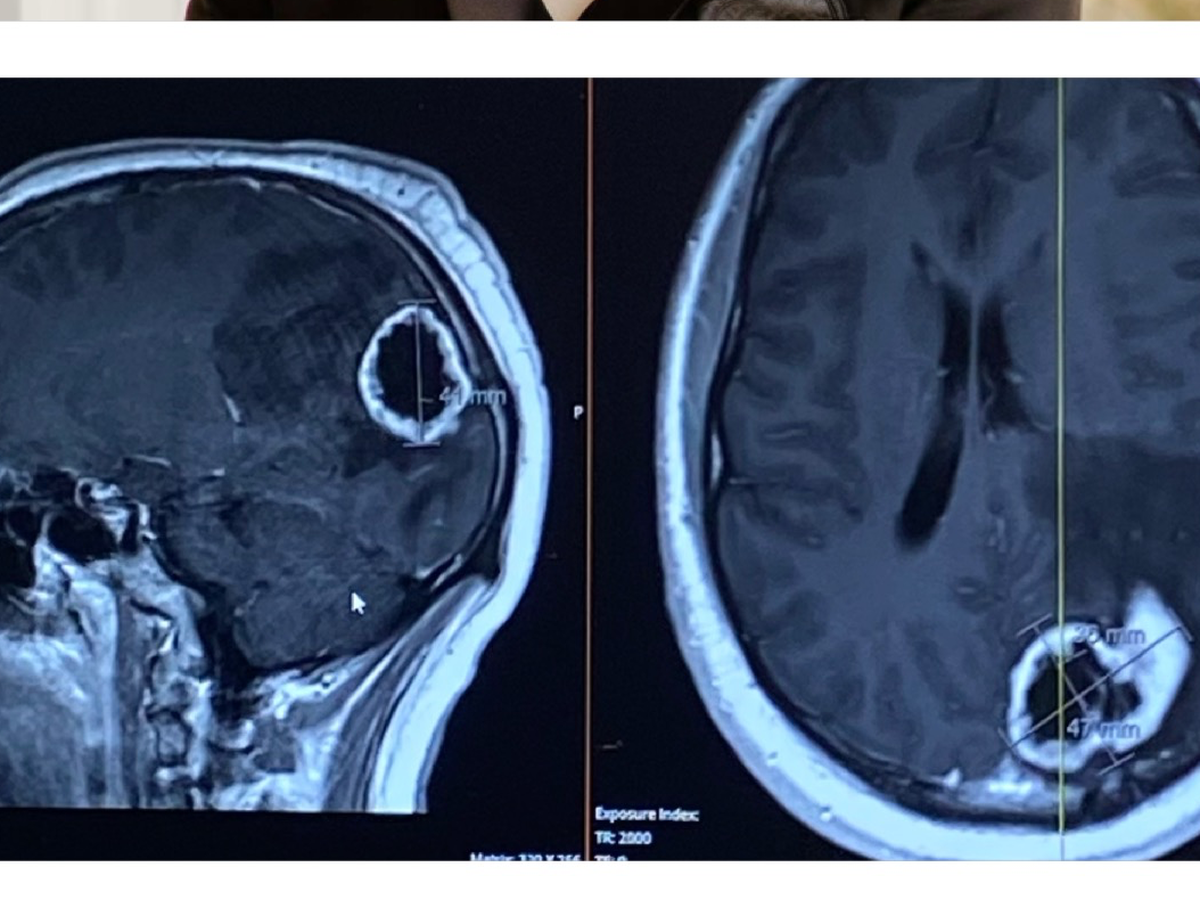

Hello! My name is Avery and I am a long-time family friend of the Koenigs. Well, actually I’m more like their adopted daughter. Eli is literally my brother from another mother. For those of you who don’t know Eli, he is only 26 and one of the kindest souls I know. Unfortunately, Elijah Koenig has been recently diagnosed with a walnut-sized brain tumor. We are unsure if it is benign or malignant, but the MRI reading suggested malignancy. He is scheduled to get his tumor, Fred (as Eli has named it), removed on Monday 8/18/25. As one can imagine, brain surgery is NOT cheap. Not only the surgery, but the hospitalization and rehabilitation afterwards. I’m hoping this GoFundMe will help relieve some financial stress that this type of situation comes with. We appreciate any amount you can give, thank you!